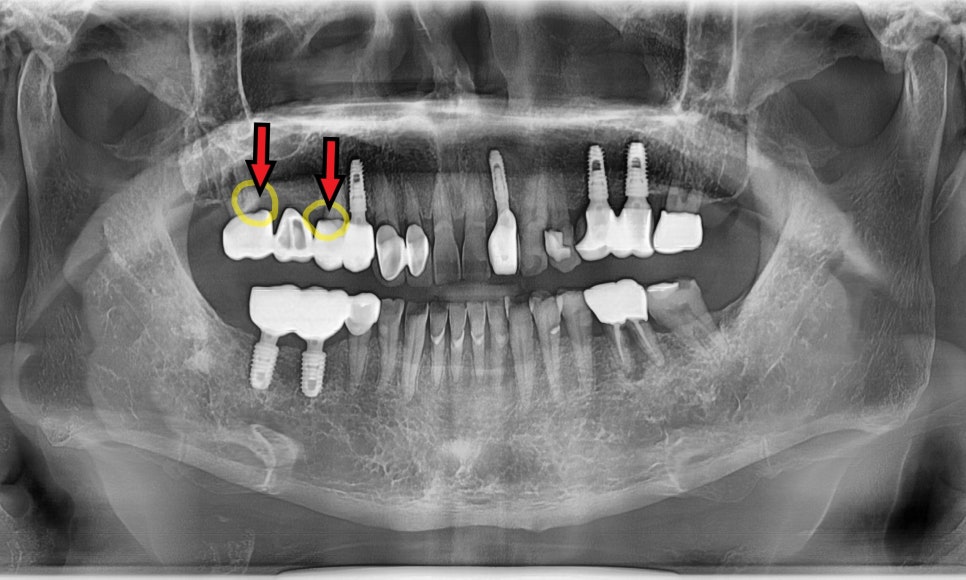

욱신거리는 어금니 때문에 찾아주신 환자분 사례

최근 한 여성 환자분께서 왼쪽 끝 어금니가

자꾸 욱신거린다며 저희 치과를 찾아주셨어요.

겉으로 보기에는 씌운 치아(크라운)가

아주 멀쩡해 보였고

환자분께서도 2년 전에

신경치료를 이미 받았던 치아라

왜 다시 아픈 건지 무척 의아해하셨는데요~

하지만 엑스레이 사진을 찍어보니

치아 뿌리 끝부분에

까맣게 나타나는 영역이 보이시나요?

뿌리 끝에 염증이 생겨 주위 뼈가 녹아내리면

방사선상에서 저렇게

까만 그림자처럼 나타납니다.

환자분이 느끼셨던 욱신거림은

잇몸 뼈 안에서 염증이 보내는 신호였던 것이죠.

재신경치료보다는

임플란트를 권해드린 이유

강동구 치아 뿌리 염증, 신경치료 한 치아인데도 아플 수 있나요?

사실 저는 자연 치아를 살리는 것을

최우선으로 생각합니다.

하지만 이분의 경우 재신경치료를 하더라도

성공률이 매우 낮고

예후가 좋지 않을 것으로 판단되었어요.

재신경치료는 이미 한 번 손을 댄 곳을

다시 청소하는 작업인데요.

기존에 채워 넣었던 단단한 재료들을

일일이 걷어내야 할 뿐더러,,,

이미 그 안에서 세균이 더 깊숙이 자리를 잡았다면

치료의 성공 가능성이 뚝 떨어지게 됩니다.

이분은 뿌리 끝 조직이 이미 헐거워진 상태라

무리하게 살리려다가는

오히려 더 큰 고생을 하실 수 있는 상황이었죠.

의사로서 소중한 생니를 포기하는 것은

참 어려운 결정이지만,,

때로는 더 큰 피해를 막기 위해

과감하게 결단을 내리는 것이

환자분께는 장기적으로 훨씬 이득이 됩니다.

그래서 이번에는 확실한 해결책인

임플란트를 진행하기로 했습니다.